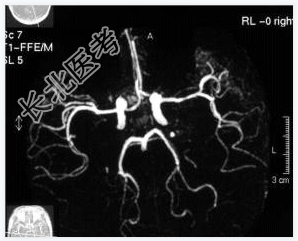

- [材料题] 患者,男性,52岁,间隙性发作情绪激动、乱语2年。一月前外院CT提示左海马高密度影,性质待定。做头颅MRI检查。